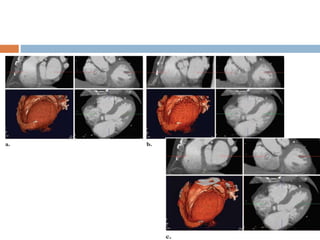

ARTIFACTS IN CARDIAC CT

 Due to factors such as tachycardia,

arrhythmia, or inappropriate scanning delay

with retrospective electrocardiographic gating.

 Cardiac pulsation artifacts

 Motion artifacts

 Misalignment and slab artifacts

 Blooming artifacts

 Respiratory artifacts

Misalignment and Slab Artifacts:

 Occur especially in patients with high heart

rates, heart rate variability, and the presence

of irregular or ectopic heart beats (e.g.,

premature ventricular contractions [PVCs] and

atrial fibrillation)

 can be best recognized in a sagittal or coronal

view.

 Often limit the diagnostic assessment of

coronary artery segments.

 One option is to reconstruct the dataset at

different phases of the cardiac cycle.